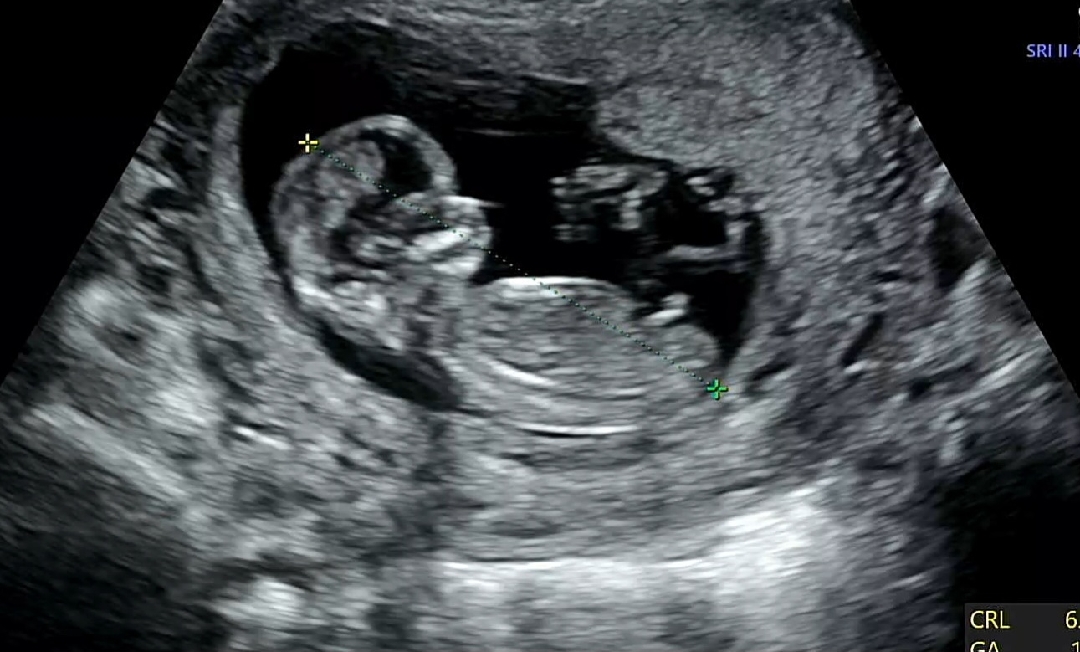

12주6일차 각도법 봐주세요~

병원에서는 아직 작아서 잘 모르겠다고만 하셔서요 어떻게 보이는지 의견 궁금합니다!